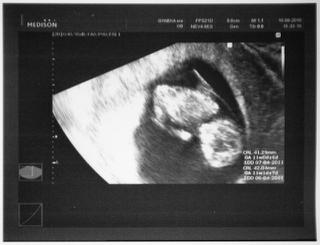

Ahojte.Tak my sme doma z prvej poradne,aj termín máme posunutý na skôr,čiže z jedenásteho na šiesteho a to podla sona,takže prepokladám,že ked sa to takto posunulo,tak bábo bude asi väčšie než bolo na prvom sone na svoj vek...neviem no...ale tak mi to vychádza 😀 máme 4,3 cm tak kočky ak viete koľko cm majú vaši chrobáčikovia tak sem sa s číslami 🙂 🙂 🙂 🙂

ahojte zienky 🙂 tak ja mam dobre spravy, dnes som bola u doktora a dostala som tehu knizku, nasa bublinka uz ma 4,1cm 😀 😵 velmi sa s drahym vytesujeme 🙂 podla poslednej menstruacie som v 10tt+4d a podla UTZ 10tt+1d 🙂

@mirrinka ahooj 🙂 aj ja so mdnes bola u doktora a nase malinke ma 4,1cm 😀 som v 11tt 🙂 podla poslednej menstruacie mi vychadza termin na 11.4 a podla sona na 6.4 😀

@brumca ahoj ja som podla sona 11+1 🙂 takže 12tt... termín 6.4 a podla poslednej MS termín 1.4. tak uvidíme ako to bude nabudúce 😀pri prvej dcérke som mala od začiatku tehotenstva termín stanovený na 1.7. a aj sa vtedy narodila 😉 😀

Pridavam fotocku nasej bublinky 🙂

@blackberry ahoj 🙂 dakujeem...stale pozeram na tu fotocku 😵

brumca - jeeej, krasna fotecka a gratulujem ku knizke.